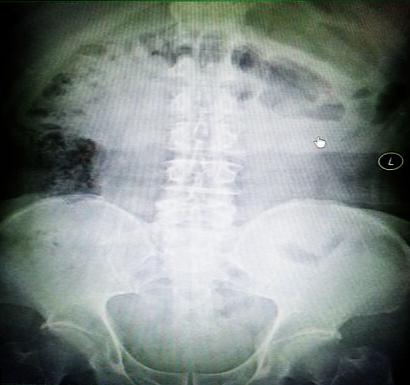

受試患者在結(jié)腸端端吻合術(shù)中,使用我司新研制產(chǎn)品達(dá)到了理想的預(yù)期效果?;颊咝g(shù)后7天、14天X光片顯影,可降解腸道支架均能按研制設(shè)計的預(yù)期時間節(jié)點保持應(yīng)有強(qiáng)度,術(shù)后21天X光片顯示可降解腸道支架已完全破碎,并排出體外。在整個試驗過程中,病患無任何不良反映,耐受良好。